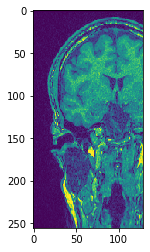

# Alternativamente, no entregue la imagen de salida y recupérela

another_slice = cle.create_2d_xy(input_image)

cle.copy_slice(input_image, another_slice, slice_index = 80)

# mostrar resultado

cle.imshow(another_slice)